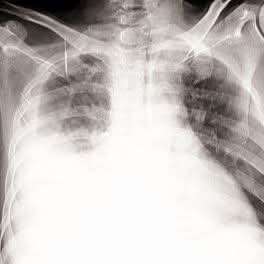

قال الدكتور وهاج المقطري:شاب ٢٤ عاما، اشتكى من ألم في صدره الأيمن منذ اسابيع، ظنه في البداية ألم عضلي بين الأضلاع، لكن مع مرور الأيام ازداد الألم وظهر عنده ضيق في التنفس فتوجه إلى أحد المستشفيات لإجراء الفحوصات،.

أظهرت الأشعة وجود تجمع سوائل في الجنب الأيمن فتم ترقيده وسحب السائل منه وأُعطي مضادات حيوية واسعة الطيف،، وتحسنت حالته لكن بعد أسبوع عاد الألم وضيق النفس من جديد،وأُظهرت الأشعة أن السوائل قد عادت الى صدره فطُلب منه إعادة سحب العينة لكنه رفض ثم جاء إلي..

شاب سليم لا يعاني من أي من الأعراض الكلاسيكية للسل، ولم يشتكي من شئ طوال حياته، ونتائج فحص السل Mantoux و  (QFT) وحتى PCR كانت سلبية وتحليل السائل الجنبي لم يظهر سل ولا خلايا سرطانية،،.!!

والحقيقة لست ادعي انني كنت ساطلب منه القيام باجراء خزعة جنبية (وهو الفحص ذو أعلى عائد تشخيصي في هكذا حالات) للتأكد اكثر من السل لولا انه قال ان والدته ماتت بالسل،،زاد دافعي أكثر علمي بان السل الجنبي احد اصعب الحالات تشخيصا فحتى فحص PCR قد يفوت التشخيص بسبب مايعرف ب (paucibacillary nature)،، فطلبت منه فورا اجراء خزعة جنبية وأقنعته بصعوبة بضرورة اجراءها..!!